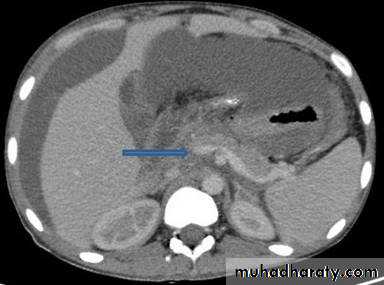

Acute Pancreatitis

CT used to

• 1. Pancreatic necrosis .• 2. An abscess.

• 3. Vascular complications.

• 4. Pseudocyst